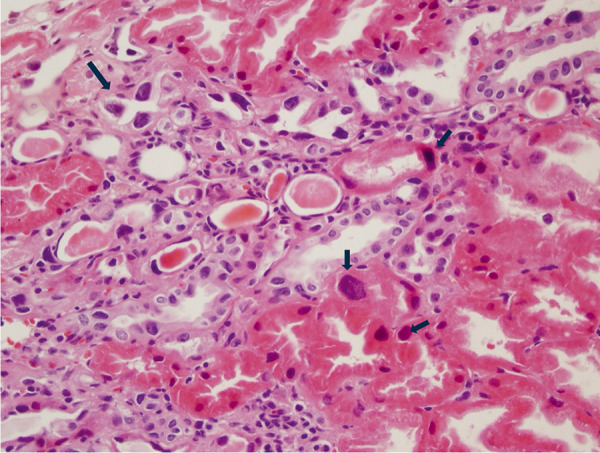

Karyomegalic interstitial nephritis (KIN) is a rare hereditary form of chronic interstitial nephritis that was first described over 50 years ago. It is characterized by karyomegalic tubular epithelial cells and progressive chronic kidney disease, often leading to end-stage renal disease by the fifth decade of life. Recent studies have identified FAN1 mutations as a key genetic contributor, with additional associations to environmental factors and toxic exposures, such as ochratoxin A, alkylating agents, and heavy metals, which may act as potential triggers of the disease. We present a detailed analysis of KIN cases, highlighting genetic diversity, clinical manifestations, and management challenges, complemented by a comprehensive review of the literature.

Abstract Image